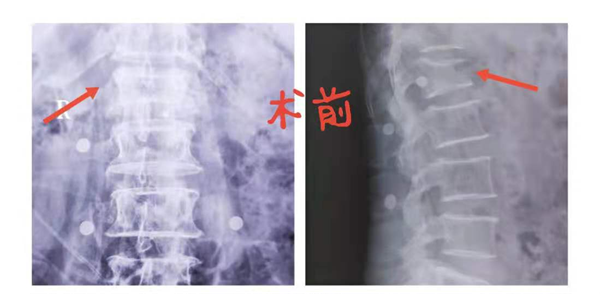

患者张某某,女,70岁。8月初下台阶时不慎摔倒,腰部受伤。伤后没有做特殊处理,在家中卧床休息,感觉腰痛症状无缓解。后来到我院骨科找王栋梁主任医师就诊,腰椎X片检查示:腰1椎体压缩性骨折。该患者宫颈癌术后18年,3年前右股骨骨折。医生查体:腰1棘突压痛明显,左下肢肿胀,左、右下肢肌力Ⅲ+级;加之该患者身体条件差,难以承受传统的开刀大手术。经过骨科王栋梁主任医师带领的医生团队,对该病例的评估、讨论,最后决定为其实施创伤小、并发症少、预后恢复快的经皮穿刺单侧椎弓根入路腰1椎体压缩性骨折椎体成形术。术后当天,患者疼痛减轻,可独立下床行走!此手术为陕健医澄合矿务局中心医院首例独立完成的脊柱微创治疗术,使医院脊柱微创技术迈上了新台阶!